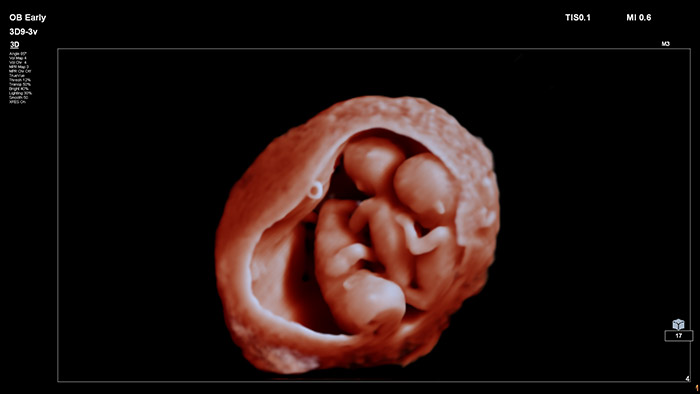

En este vídeo, el Dr. Michael Ruma presenta el transductor V9-2 para ultrasonidos 3D de Philips. El V9-2 es el primer transductor mecánico PureWave para ultrasonidos 3D de la división de ultrasonidos de Philips específico para obstetricia/ginecología y ofrece una extraordinaria calidad de imagen y un diseño ergonómico avanzado. El V9-2 está especialmente indicado para la adquisición de imágenes 2D, 3D y 4D para exploraciones obstétricas del primer, segundo y tercer trimestre..